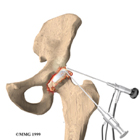

I pazienti in cui l’osteonecrosi è diagnosticata in una fase molto precoce (prima del collasso della testa femorale) sono buoni candidati per le procedure di conservazione dell'anca.

La cosiddetta core decompression consiste nel perforare la testa femorale attraverso mini-incisioni e asportare la parte di tessuto osseo andata in necrosi sostituendola con trapianti ossei autologhi, omologhi o con sostituti ossei. Un aiuto biologico tramite cellule staminali o concentrati piastrinici favoriscono la rivascolarizzazione della zona e quindi la rigenerazione ossea e cartilaginea.

Un'altra opzione chirurgica è quella di utilizzare un trapianto di perone vascolarizzato. Si tratta di una procedura più complessa, in cui viene prelevato con tecniche microchirurgiche il perone con il peduncolo vascolare dall'arto controlaterale e successivamente innestato all'interno della testa del femore per favorire la guarigione della zona di osteonecrosi.